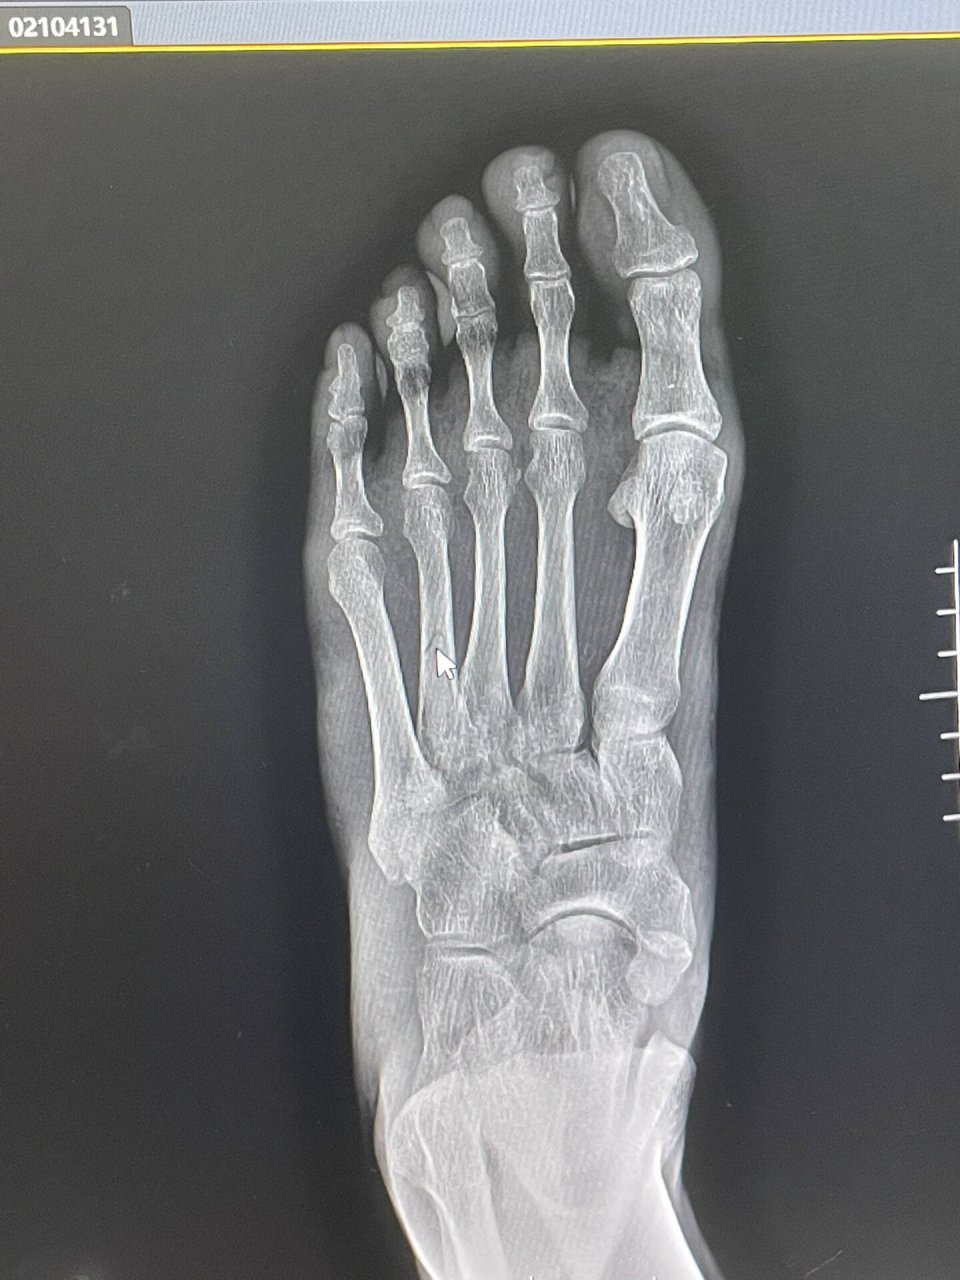

门诊遇到的一例跖骨骨折

图片尺寸3024x4032